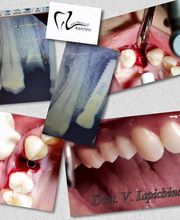

Galleria

Gallery Cliente